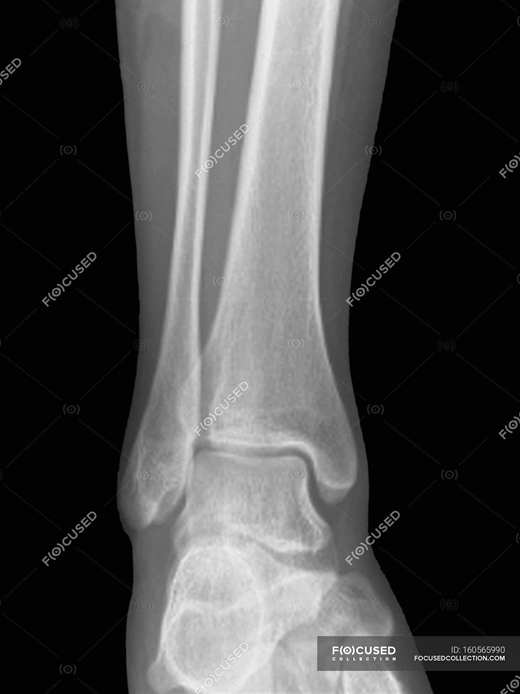

ЯК НАЗИВАЄТЬСЯ ЦЯ КІСТКА?

варіанти відповідей

FIBULA

TIBIA

HUMERUS

RADIUS

ULNA

CLAVICULA

STERNUM

FEMUR